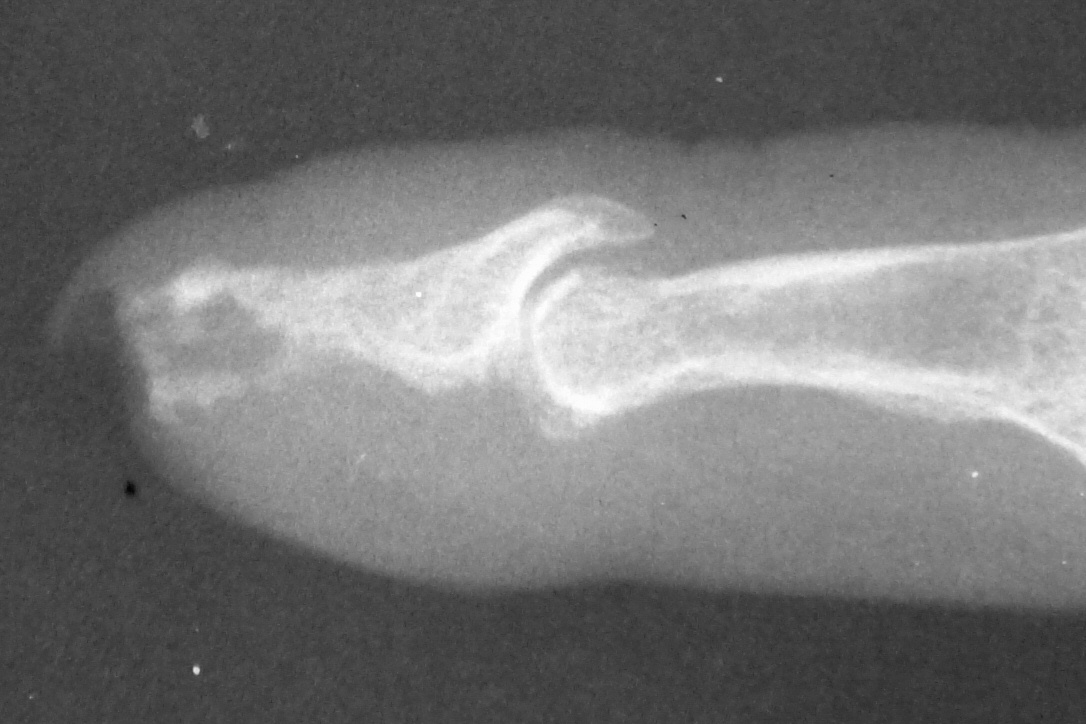

Xrays over this period: initial deformity, bone graft, and progressive bone graft loss over the course of years:

Image Image